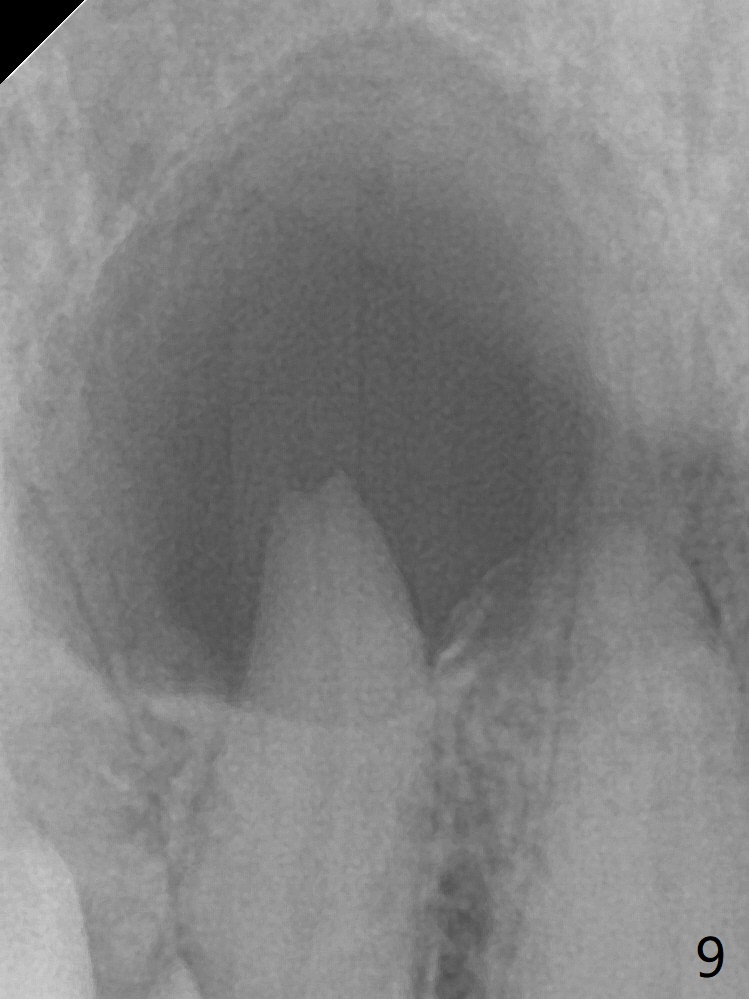

A 47-year-old woman (dental phobic) presented to clinic 9.5 years ago with periapical radiolucency (PARL) at #7 and 9 (Fig.1). RCT was done at #9 because of fistula and symptom 6 months later (Fig.2). While PARL increases at #7 without symptom, that at #9 disappears 8.5 years postop. Three months later, the patient returns for #7 RCT because of the abscesses (Fig.4 *) and pain. Intraop PA is taken with a 30/.06 rotary file in the canal with 19 mm working length (Fig.5). After use of #15 hand file for 20 mm, Ca(OH)2 paste is applied in the canal. When the rubber dam is removed, the abscesses enlarge (Fig.6), which may be related to sodium hypochlorite leakage. A dental explorer is used to try to find a bony opening to the large PARL without success (Fig.7). A postop PA reveals the leakage of Ca(OH)2 paste (Fig.8). Review of the preop PA (Fig.3,9) and intraop PAs (Fig.5,10) shows possible apical resorption and open apical foramen, which is the basis for the paste leakage (Fig.8,11). Careful analysis (with magnification and room light off) of pre- and intra-op PAs should be able to avoid use of #15 hand file out of apical constriction and the complication. The abscess has receded 1 month later (Fig.12). The paste has been resorbed 1 month later (Fig.13). A 30/.06 Gutta Percha is inserted at 18.5 mm (Fig.14 vs. 30/.06 file at 19 mm, 15 file at 20 mm last visit). Fig.15 is the final PA after closure of the access with composite (Fig.15).